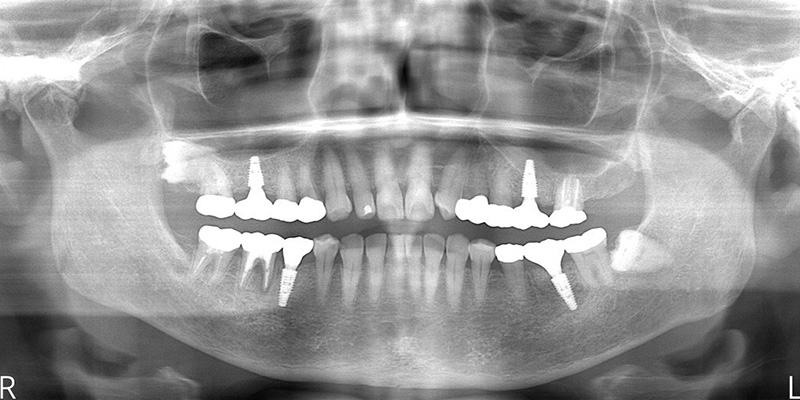

| 診査診断 | 上顎歯牙欠損、歯周病、不良補綴、根尖性周囲炎。 不正咬合により噛み合わせのバランスが悪い事が原因により咬合治療が必要。 |

| 治療内容 | 欠損部インプラント 不正咬合に対し不良補綴のやり直しと合わせて咬合再構築 |

| 治療期間 | 4ヶ月 |

| 費用 | 200万円 |